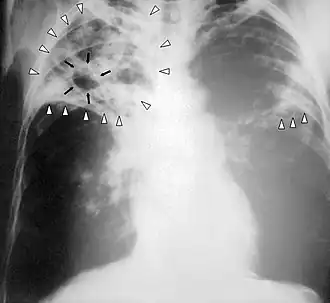

![]() Рентгенограмма органов грудной клетки больного туберкулёзом лёгких с распадом | |